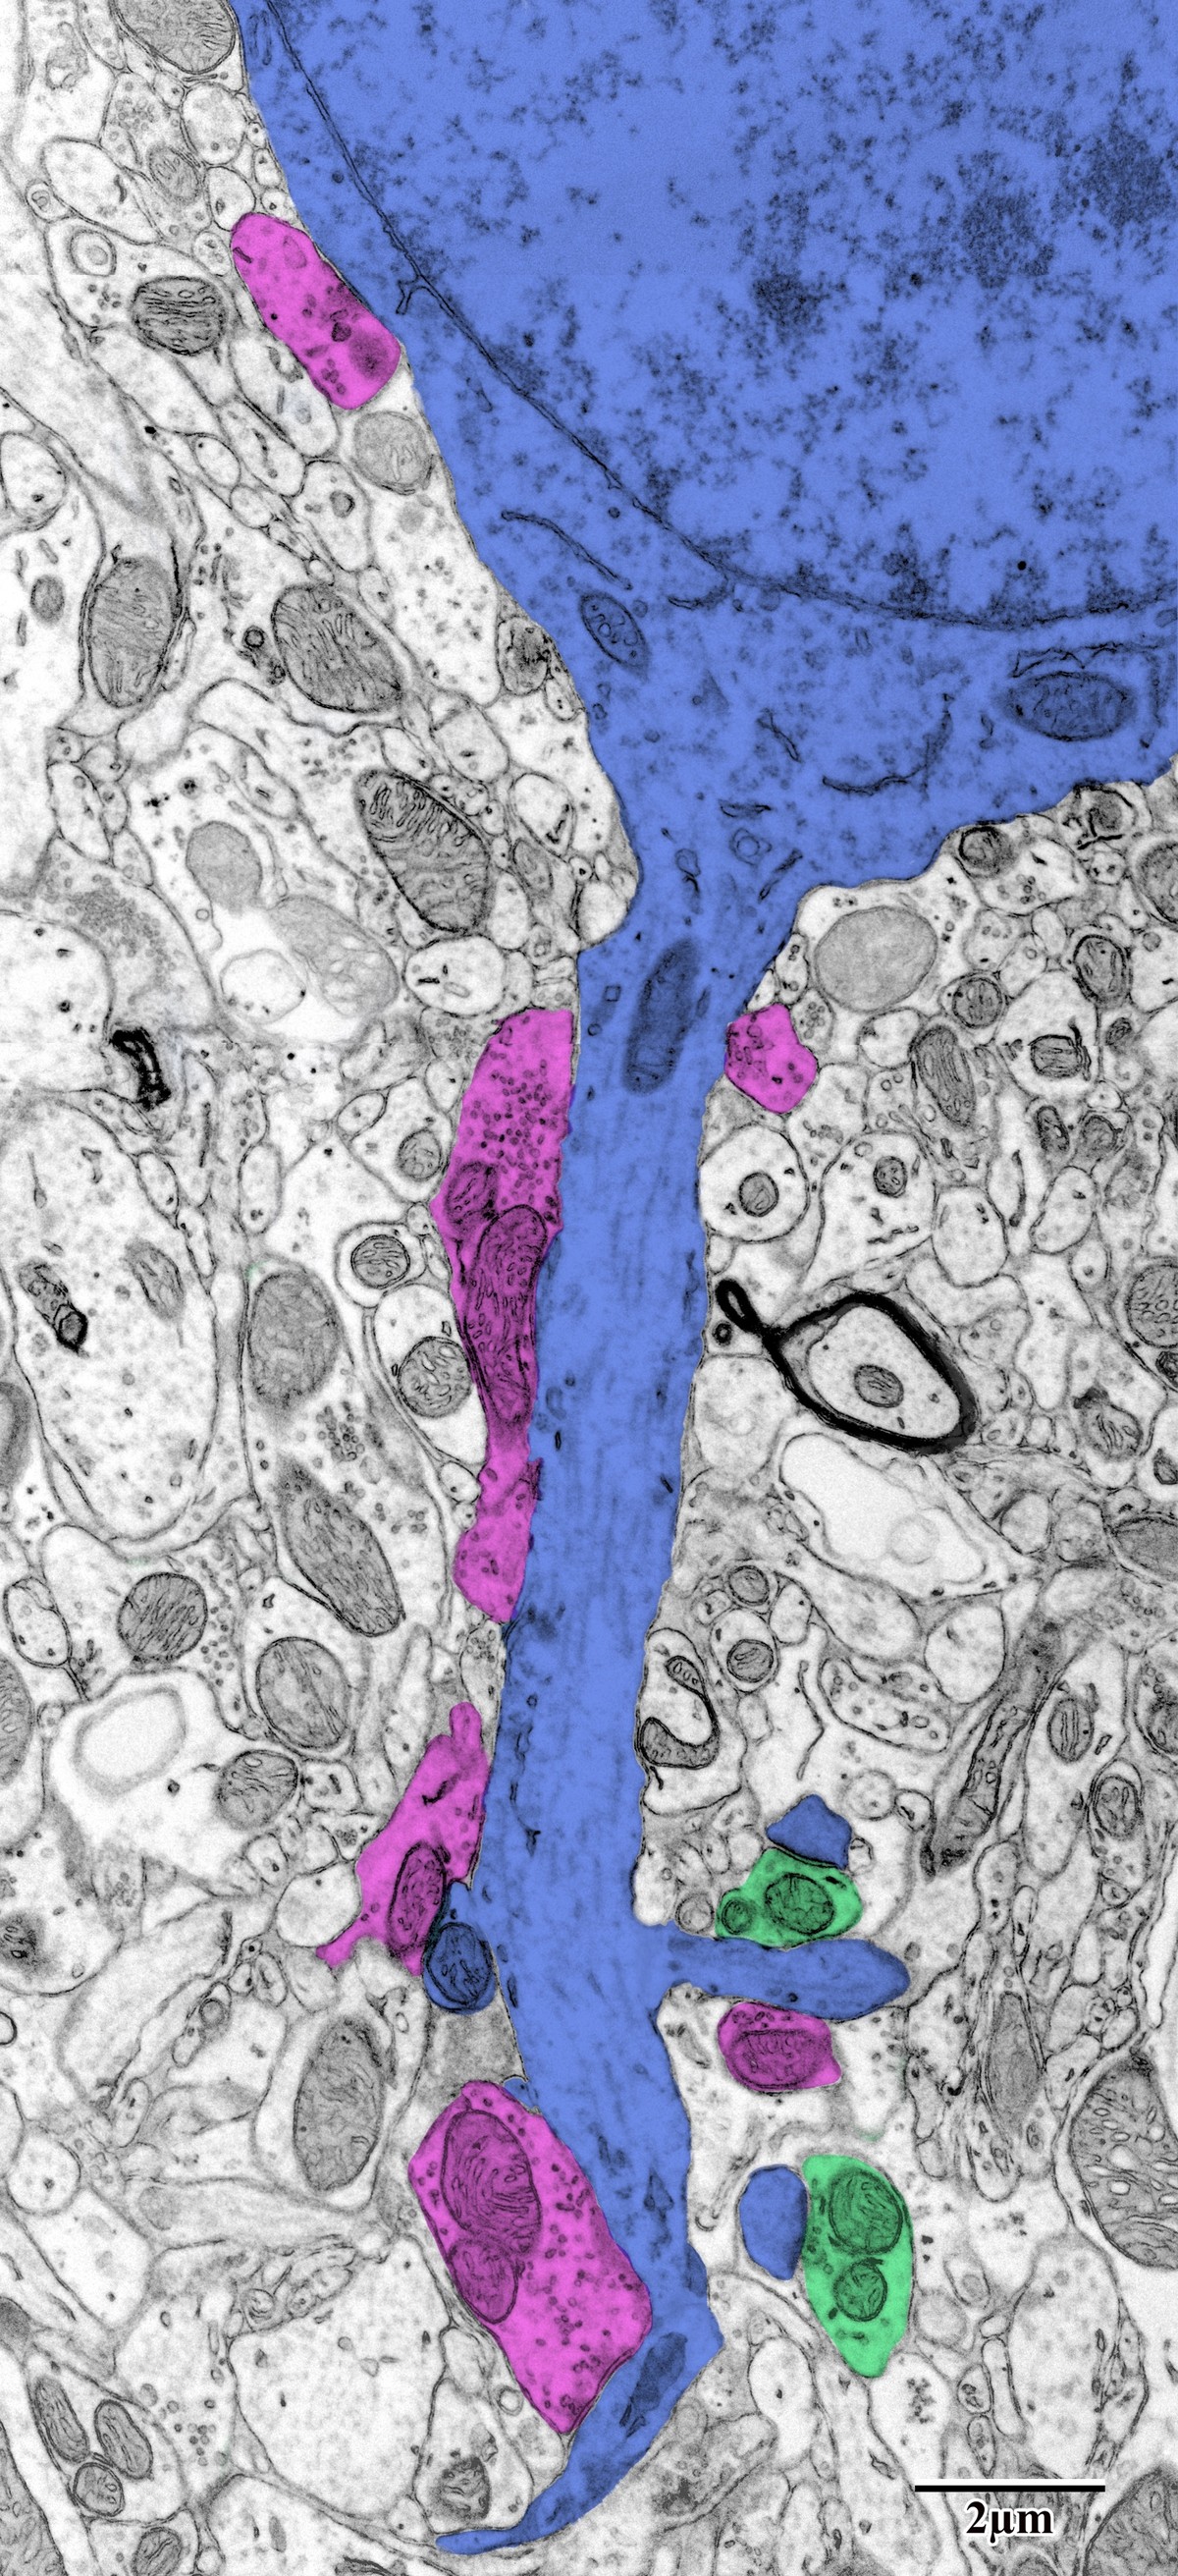

Transmission Electron Microscopy

Ultrathin sections (70–80 nm) were cut with a Diatome diamond knife on the UltraCut E, collected on 200-hex copper mesh grids, and imaged at 80 kV on a JEOL JEM-1400 TEM equipped with a Gatan Orius SC1000 CCD camera (4008 × 2672 px). Key subcellular structures were pseudocolored in Adobe Photoshop to enhance visualization and enable morphometric quantification in ImageJ.

Synaptic Classification

Synapses were classified and pseudocolored for morphometric analysis. Presynaptic terminals (green) contain synaptic vesicles and interface with postsynaptic structures (blue). The dendrite shown here features multiple synaptic contacts including both excitatory (round vesicles, large PSD) and inhibitory (flattened vesicles) types.

Pseudocolored pyramidal neuron dendrite with synaptic contacts

Pyramidal neuron dendrite (blue) with associated mitochondria (pink/red) and synaptic contacts (green presynaptic terminals). From Bayati, BSc Honours Thesis 2018.